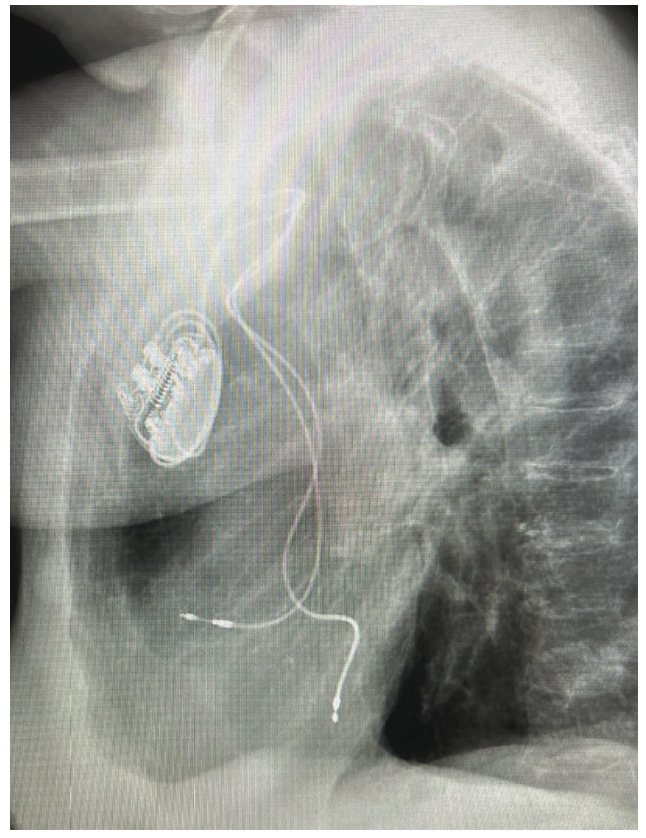

The patient is a 60-year-old female with sick sinus syndrome and a permanent dual-chamber pacemaker (Ingevity MRI pacing lead (model/length 7741/52 cm and 7740/46 cm, Boston Scientific) implanted 5 years prior. She was admitted for heart failure (HF) with an ejection fraction (EF) of 40%, atrial fibrillation (AF), and moderate mitral regurgitation (MR). The chest x-ray showed the ventricular lead to be in the left ventricle (LV) via the atrial septum (Figures 1 and 2). She was referred to us for extraction and device revision. The case raised several questions as to management of HF, AF, and an abnormally located lead impinging upon the mitral apparatus. Surgical extraction of the lead was discussed as well. As the onset of HF coincided with AF, and considering that the patient could require atrial septal device (ASD) closure after extraction, it was recommended that the patient first undergo AF ablation before extraction. She underwent pulmonary vein isolation and additional LA posterior wall and cavotricuspid isthmus ablation at our institution. Intraprocedural transesophageal echocardiography (TEE) allowed us to confirm the aberrant course of the lead and impingement on the mitral apparatus. Keeping in mind the relative urgency due to MR, she was scheduled for extraction 3 weeks later. Apixaban was held on the morning of the procedure and resumed post procedure the same evening. The case was coordinated with the interventionalist, cardiothoracic (CT) surgeon, and neurointerventional radiologist, anticipating potential issues such as development of a large ASD post extraction that could require a closure device, mitral apparatus damage resulting in acute MR and decompensation, and cerebral embolization of debris. In addition to the usual femoral sheaths (discussed later), the Sentinel Cerebral Protection System (Boston Scientific) was positioned prophylactically via the right radial approach by the interventionalist in the hybrid room (Figure 3). TEE imaging did not reveal any thrombus or vegetations on the lead body. A 12 French (F) GlideLight Laser Sheath (Philips) was used along with a VisiSheath Dilator Sheath (Philips). Laser applications were performed along the lead, specifically in the innominate vein and to cross the atrial septum. The VisiSheath was used to break adhesions along the mitral annulus and LV apex. A larger (14F) sheath may have theoretically allowed less shearing of debris and embolization risk, with the potential downside of creating a larger ASD. In a more chronically implanted lead, this issue may be taken into consideration when selecting sheath size. The lead came out with countertraction at the LV apex. A residual patent foramen ovale was seen that was small and did not require closure. MR was negligible with no visible damage to the mitral valve leaflets or chordal apparatus. The new right ventricular (RV) lead was implanted on the RV septum, confirming position by orthogonal fluoroscopic views and TEE. The patient had intact conduction with a narrow QRS and the decision was made not to implant a conduction system pacing lead; instead, the RV lead was positioned on the RV septum. No debris was seen in the Sentinel device after removal and careful examination. She was discharged home the next day with an uneventful postop course. She remains symptom free without further AF or HF after 6 months and has a normalized LVEF.